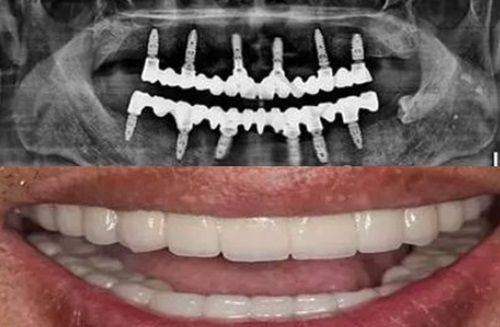

此外,徐州口腔医院allon4半口种植牙价格4万元起,全口种植牙价格8万元起。与其他地区的口腔医院相比,徐州口腔医院的种植牙价格是不高的。同时,徐州种植牙好的医院还有特别多,如徐州医 大鼎植口腔、徐州紫浩口腔、徐州诺恩口腔等,这些医院均是徐州正规便宜又好的口腔医院。